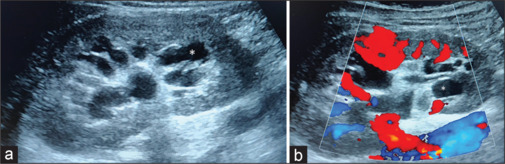

肾淋巴管扩张是一种良性疾病,其特征是肾脏淋巴管囊性扩张。它可发生在肾周、肾窦和肾内。我们描述一个罕见的病例肾窦淋巴管扩张与特征性的影像学表现在一个25岁的女性。她表现为腰部疼痛,并进行了保守治疗。

Renal lymphangiectasia is a benign disorder characterized by cystic dilatation of lymphatic channels in the kidney. It can occur in the perinephric, renal sinus, and intrarenal locations. We describe an uncommon case of renal sinus lymphangiectasia with a characteristic imaging appearance in a 25-year-old female. She presented with loin pain that was managed conservatively.